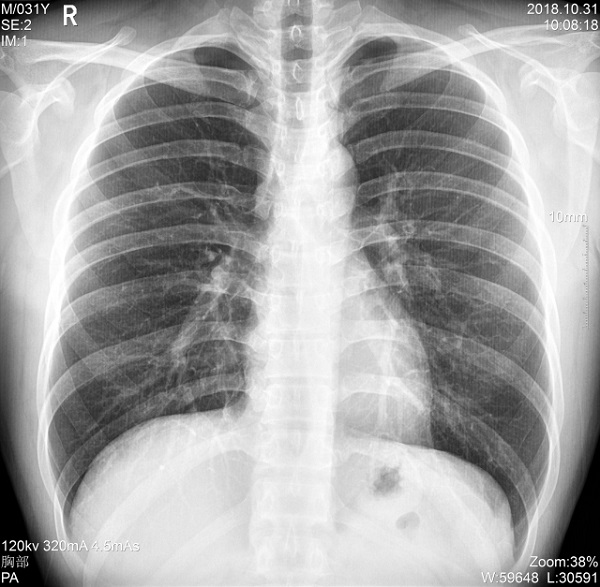

三、支持高千伏攝影 肺部紋理更有層次

PLX5500的最大可調(diào)千伏達到150kV,在達到一定高電壓后,與骨骼相重疊的軟組織或骨骼本身的細小結(jié)構(gòu)及含氣的管腔等,均可清晰顯示。